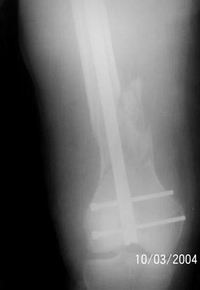

The femur injury was treated by long retrograde interlocking nail.

It was used ORTHFIX Retrograde nailing System, diameter 11.